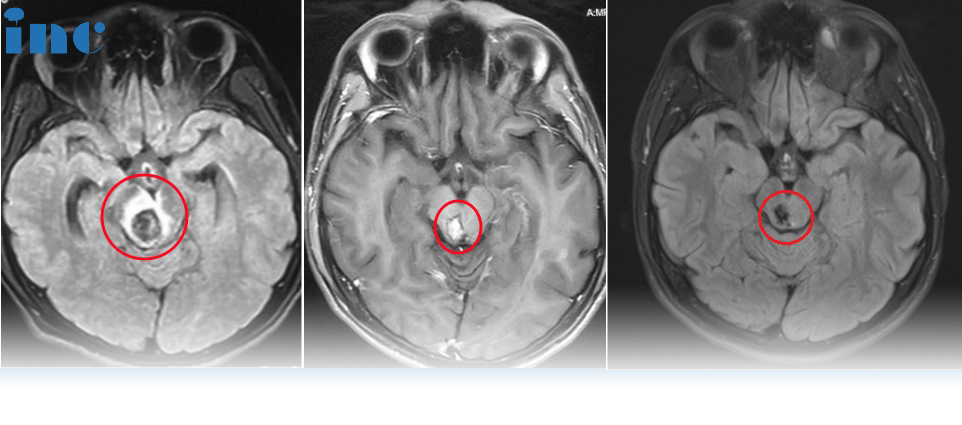

很用力咳嗽了几下,还咳出了脑干出血?真有这样的事吗? 41岁的宋女士于2023年10月底,因感冒喉咙有痰,很用力咳嗽了几下,随后出现视物模糊,重影,耳鸣,四肢乏力,犯困,嗜睡...